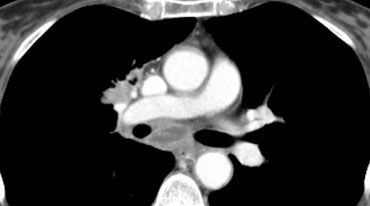

Ví dụ:

- Một khối u T4 điển hình ở thùy trên phổi phải với xâm lấn trung thất.

- Xâm lấn động mạch phổi phải.

- Xâm lấn carina.

- Xâm lấn nhĩ trái.